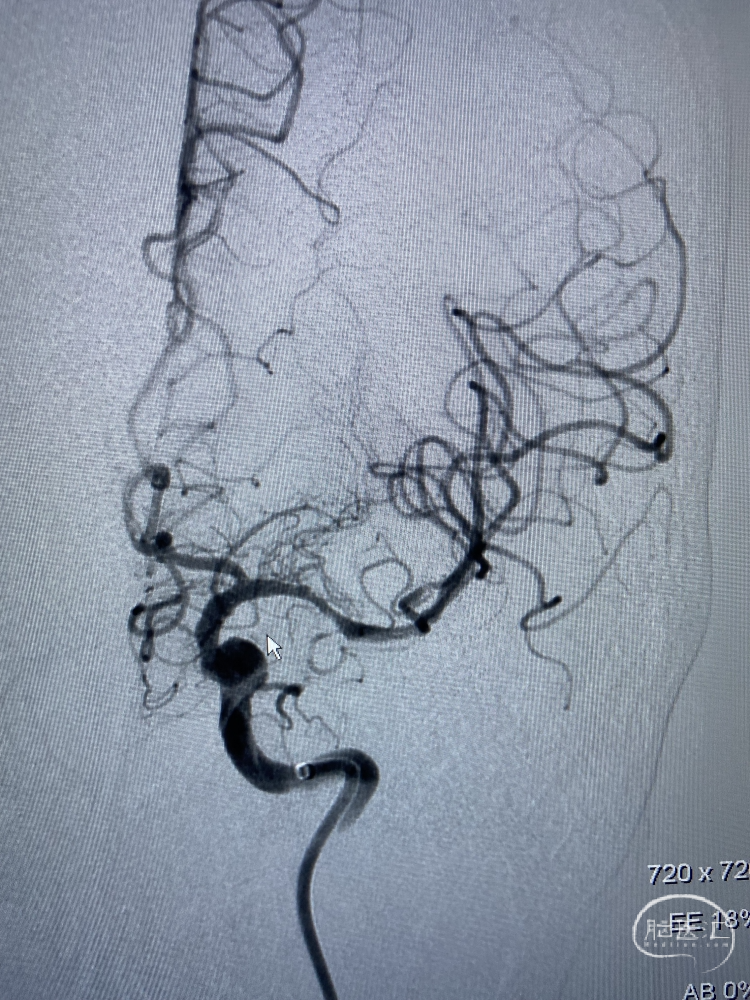

麻醉满意后,造影明确患者为Ⅲ型弓,血管迂曲,行左侧锁骨下造影示:左侧椎动脉开口处轻度狭窄,狭窄率约30%,超选入左椎动脉,造影示:左椎动脉及基底动脉走形正常,基底动脉、双侧大脑后动脉及小脑上动脉通畅,走形正常,前向血流TICI 3级。左颈总动脉及左侧颈内动脉走形正常,左侧大脑中动脉M1闭塞。撤出造影管。

以泥鳅导丝携带8F Guiding及多功能造影管路图下同轴到颈内动脉,撤出多功能管。ASAHI-0.014in×200cm微导丝携带Navien-72及SL-10微导管到达颈内动脉末端,微导管造影再次证实大脑前动脉通畅,左侧大脑中动脉M1闭塞,微导丝通过闭塞段顺利证实为真腔,中间导管造影提示远端血流存在,前向血流缓慢,M1处重度狭窄,交换Transed 0.014in×300cm微导丝,经微导丝上Gateway 2.0mm×15mm球囊,与M1狭窄处行6ATM缓慢扩张,观察前向血流有所好转,于微导管处行替罗非班5ml缓慢注射接触性溶栓,观察5分钟,血管有所回弹。

再次给予Gateway球囊以6ATM压力缓慢扩张,并缓慢注射替罗非班5ml,观察20分钟,M1处血管毛糙,血管回弹明显,给予经微导管释放Neuroform Atlas 4.0mm×21mm支架满意。复查造影左侧大脑中动脉及大脑前动脉显影良好,mTICI3级,观察10分钟后,再次复查造影左侧大脑中动脉及大脑前动脉显影良好。行Dyna CT见未见明显出血灶。

术中DSA:左侧颈内动脉正侧位,M1闭塞

ASAHI微导丝携带Navien-72及SL-10微导管,造影血管通畅,前向血流缓慢,给予Gateway 2.0mm×15mm球囊球扩

观察血管有所回弹,给予Gateway球囊以6ATM压力缓慢扩张,并缓慢注射替罗非班5ml

Neuroform Atlas 4.0mm×21mm支架释放满意

术后左颈内正侧位

常规静脉溶栓、动脉取栓及静脉溶栓+动脉取栓均已非常成熟。本例患者准备术中取栓,但微导丝通过后造影显示远端血管通畅,近端Navien及远端微导管返流均证实M1为重度狭窄后闭塞,无需取栓,给予颅内球囊扩张+替罗非班抗凝后有所好转。但前向血流差,再次球扩后观察20分钟,仍需贴附支架,术中证实效果明显。